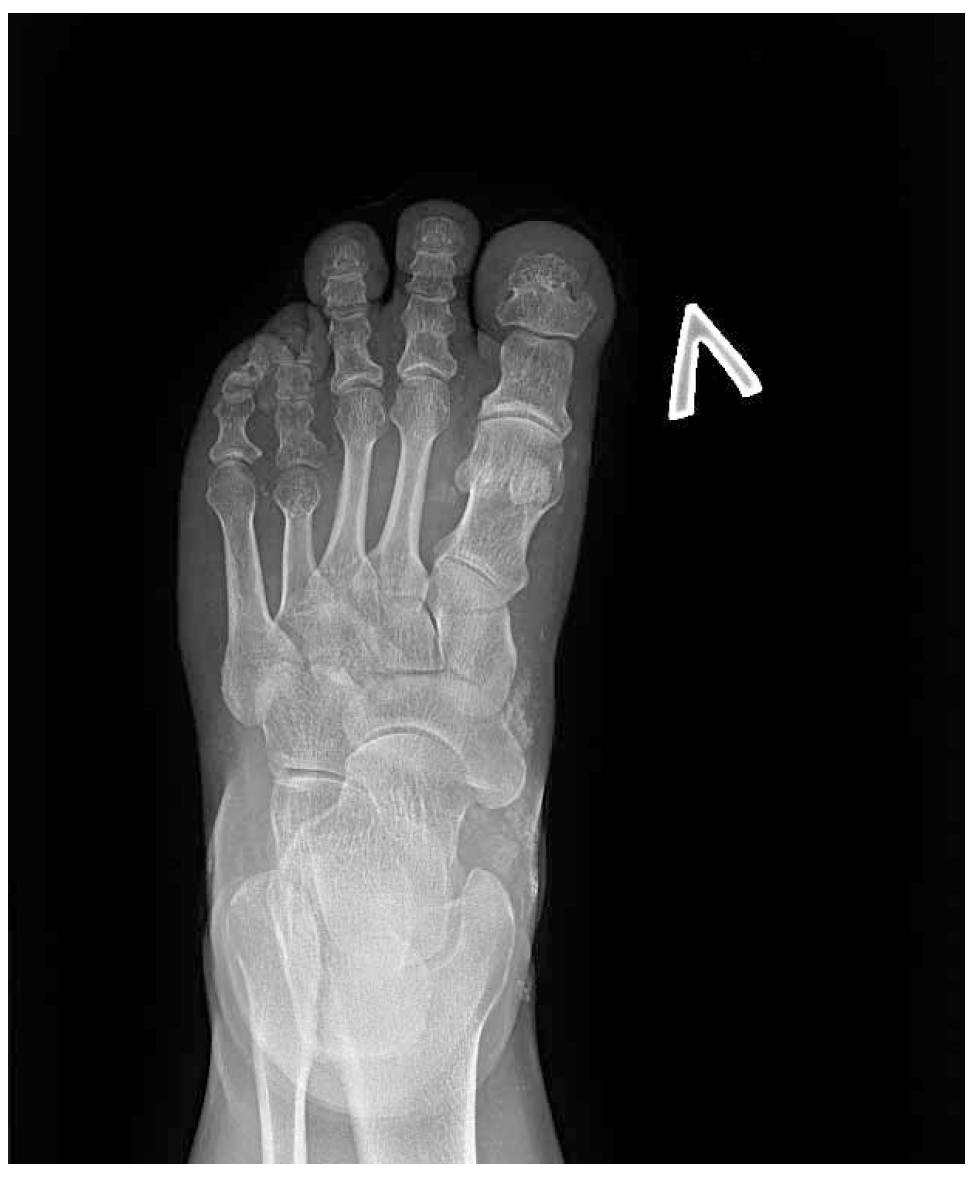

В ФГБУ НМИЦ эндокринологии наблюдается женщина 35 лет с ожирением, низкорослостью, депрессивными расстройствами, нарушениями кальций-фосфорного обмена, гипотиреозом. С 3 лет у пациентки отмечались тонические судороги на фоне фебрильной лихорадки и периодические миалгии. Впервые обследование проведено в 12 лет в связи с появлением карпопедальных спазмов, когда была выявлена гипокальциемия (Са общ. 1,3, при норме 2,0–2,6 ммоль/л), гиперфосфатемия (2,66 ммоль/л при норме 0,7–1,6) на фоне повышенного уровня ПТГ (268 пг/мл). Во время обследования в стационаре также впервые обратили внимание на особенности фенотипа: у девочки отмечалось ожирение, укорочение IV и V пястных и плюсневых костей (рис. 1, 2), пальпировались плотные подкожные образования, не спаянные с окружающей тканью, безболезненные. Гистологическое исследование биоптата образований доказало наличие подкожных кальцификатов с распространением в перимизий. По данным мультиспиральной компьютерной томографии (МСКТ) головы выявлено обызвествление базальных ядер и субкортикальных отделов головного мозга (рис. 3). Был установлен диагноз «псевдогипопаратиреоз Iа типа». Молекулярно-генетическое исследование подтвердило наличие мутации в гене GNAS – гетерозиготная мутация GNAS в сайте сплайсинга с.585+2Т>С. По поводу резистентности к ПТГ назначен альфакальцидол, в последующем к терапии были добавлены препараты кальция. Прием препаратов осуществлялся под контролем показателей кальция крови с периодической коррекцией дозы. В 20 лет впервые выявлен субклинический гипотиреоз и назначена заместительная терапия препаратом левотироксина натрия с дальнейшей коррекцией дозы в зависимости от уровня ТТГ при контроле в динамике. Клинических признаков гипогонадизма не отмечалось: менархе в 12 лет, менструальный цикл регулярный. При сборе семейного анамнеза не было выявлено особенностей, указывающих на возможность наличия у родственников НОО или гипокальциемии: родители нормального роста, брахидактилии, подкожных образований у них не имеется, судорожных эпизодов или криптогенной эпилепсии ни у родителей, ни у ближайших родственников не отмечалось. У пациентки нет детей, но было 4 беременности, все окончившиеся абортами. Одна беременность – замершая, один аборт по желанию пациентки, 2 последние беременности были прерваны после получения результатов пренатальной диагностики, доказавшей наличие у плода той же мутации в гене GNAS, что и у матери.

Рис. 1. Брахидактилия: выраженное укорочение V пястной кости слева.

Рис. 2. Брахидактилия: укорочение IV плюсневой кости слева.